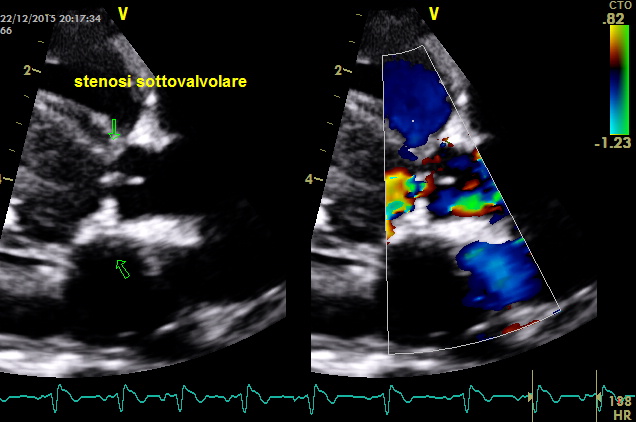

come si puo’ notare dai particolari nelle immagini zoom la struttura valvolare appare integra con una normale conformazione delle cuspidi la turbolenza e’ generata da una piccola banda fibrosa sottovalvolare ,in questo caso a dispetto delle alterazioni minime visualizzabili nell’esame B mode la stenosi sulla base del gradiente appare severa ,il PHT inferiore ai 300mm/sec dell’insufficienza aortica che quasi sempre accompagna la stenosi indica pressioni diastoliche nel ventricolo sx elevate

– Classe 1: l’endocardio del setto interventricolare si presenta ispessito e forma piccoli noduli (1-2 mm); talvolta questi piccoli noduli sono presenti anche sulla superficie inferiore dei lembi aortici. Questa lesione corrisponde alla stenosi suboartica discreta della classificazione ecocardiografica (tipo 1).

– Classe 2: l’endocardio sottovalvolare presenta un ispessimento fibroso sottovalvolare che riveste quasi completamente il tratto di efflusso, partendo dalla base del lembo anteriore mitralico e si estende al setto interventricolare. Questa forma corrisponde, nella classificazione ecocardiografica, all’ostruzione ad anello fibroso (tipo 2)

– Classe 3: la proliferazione endocardica sottovalvolare forma un restringimento di tutto il tratto di efflusso in senso circonferenziale e per tutta la sua lunghezza. Questa lesione, in ecocardiografia, viene classificata come stenosi subaortica a tipo tunnel (tipo 3).Seguendo la classificazione di Pyle la morfologia di questo caso non appare inquadrabile del tutto in quanto non si visualizzano noduli e neanche un ispessimento fibroso che riveste “quasi del tutto” il tratto di efflusso ,il cercine appare limitato al tratto prevalvolare .Bisogna considerare che la stenosi sub-aortica e aortica sono propagate nelle razze e nelle famiglie con base genetica; tuttavia non si conoscono completamente le modalità di trasmissione. Possiamo dire che non è propriamente una malattia congenita perché le lesioni possono non essere presenti alla nascita o, in qualunque caso, non completamente sviluppate. Per questo motivo, una stadiazione clinica non deve essere effettuata prima degli 8-12 mesi di età.